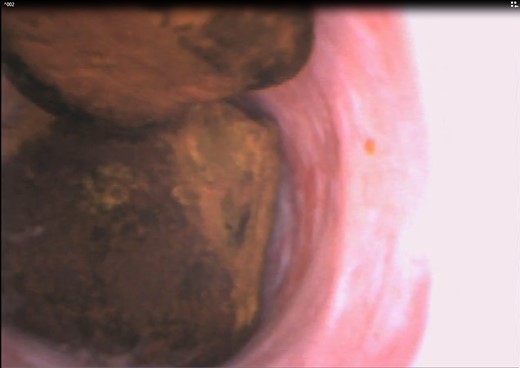

Using reusable videoendoscopes for that purpose always raises the question of the ergonomy of use, and easy image capture. In that respect, the Ambu® aScope 3™ clearly exceeded the challenge. The image quality is also comparable to that of conventional choledochoscopes (Figs 1 and 2).